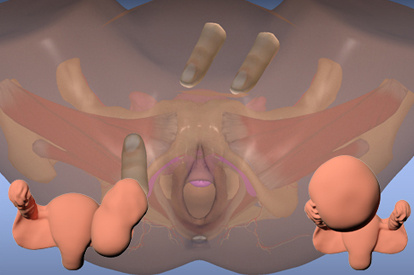

The PELVIC Mentor allows nurses, nurse practitioners, Doctorate Of Nursing Programs (DNP), certified nurse midwives, OB/GYNs, family practice doctors, physician assistants, medical students, and physician assistant learners to obtain detailed knowledge of pelvic anatomy and to acquire the comprehensive skills required to perform pelvic exams.

- Practice on pathologies not found with standardized patients and other simulators

The self-study training module has led to substantial improvements in internal rating with a proportion of structures recognized from 31.25 to 87.5 %. The preliminary results suggest that the 3D virtual simulator enhances and facilitates learning the anatomy of the pelvic floor.